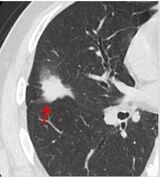

肺がんのCT画像。矢印の先にある「がん」(画像:株式会社ワイズ・リーディング提供)